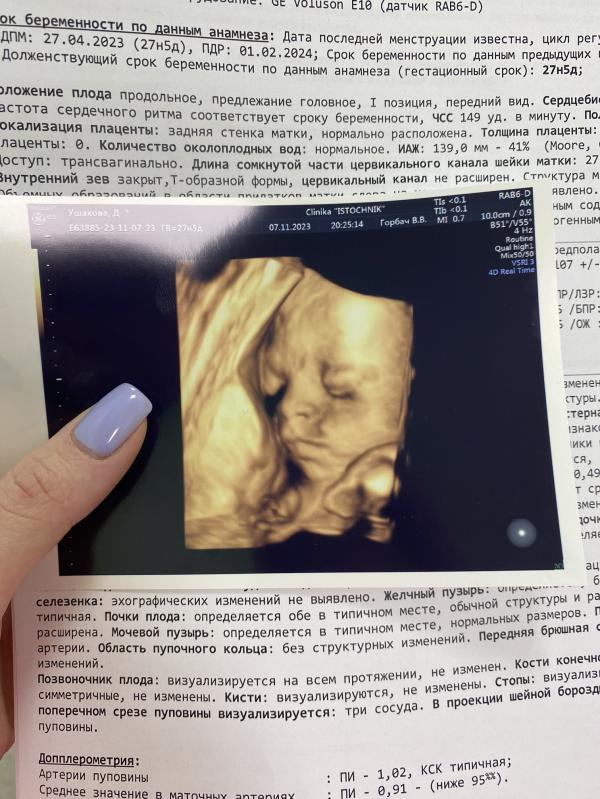

Малыш уже весом 1100🥹

В принципе всё хорошо, а то я переживала, что из-за гсд начиталась там всякого про многоводие и прочее.

Шейка правда сказали короткая, завтра иду к своему врачу в ЖК ..сказали надо устанавливать кольцо. Ну как я поняла-это частое явление и по сути ни чего страшного, хорошо что вовремя заметили. Думаю не стоит сильно переживать? Кольцо поставят и доношу нормально?